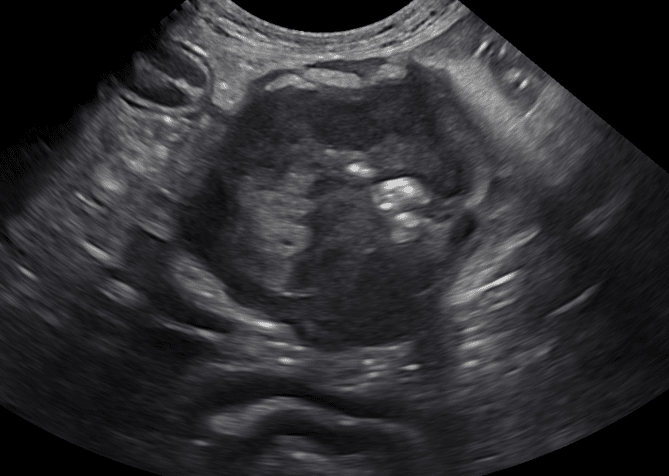

Figure 1c (above): Example of an asymmetric, circumferential small intestinal mural mass diagnosed as lymphoma.

Small intestinal abnormalities on ultrasound can be broken into two main categories: focal and diffuse disease. Focal small intestinal lesions include mechanical obstruction caused by foreign material, intussusception, or a mass. Masses are described as circumferential, asymmetrically circumferential, or eccentric (Figures 1a-1c). In dogs, one study noted that 99% of dogs with intestinal neoplasia have a loss of wall layering; unfortunately, there can be some overlap between benign and malignant masses on ultrasound. The more common intestinal mass neoplasms include adenocarcinoma, lymphoma, gastrointestinal stromal tumor, leiomyosarcoma, leiomyoma, and mast cell tumor. In cats, the most common intestinal masses are lymphoma or adenocarcinoma, followed by mast cell tumors. Lymphoma can present as solitary or multiple masses or a diffuse altered wall layering. Carcinomas most often are transmural lesions with loss of wall layering and can result in the narrowing of the lumen and secondary mechanical ileus. Mast cell tumors most commonly present as a focal mass that is hypoechoic and either eccentric or asymmetrically circumferential, similar to other intestinal neoplasms, and is rarely reported as a diffuse intestinal wall thickening. An interesting point documented in cats is that mast cell tumors in the intestine can often alter but not completely disrupt the wall layering. In dogs, it has been reported that there are no ultrasonographic signs to help differentiate between gastrointestinal spindle cell tumor types as they most often are seen as eccentric and bulging out of the serosa; however, gastrointestinal stromal tumors were more commonly seen in the cecum and large intestine.